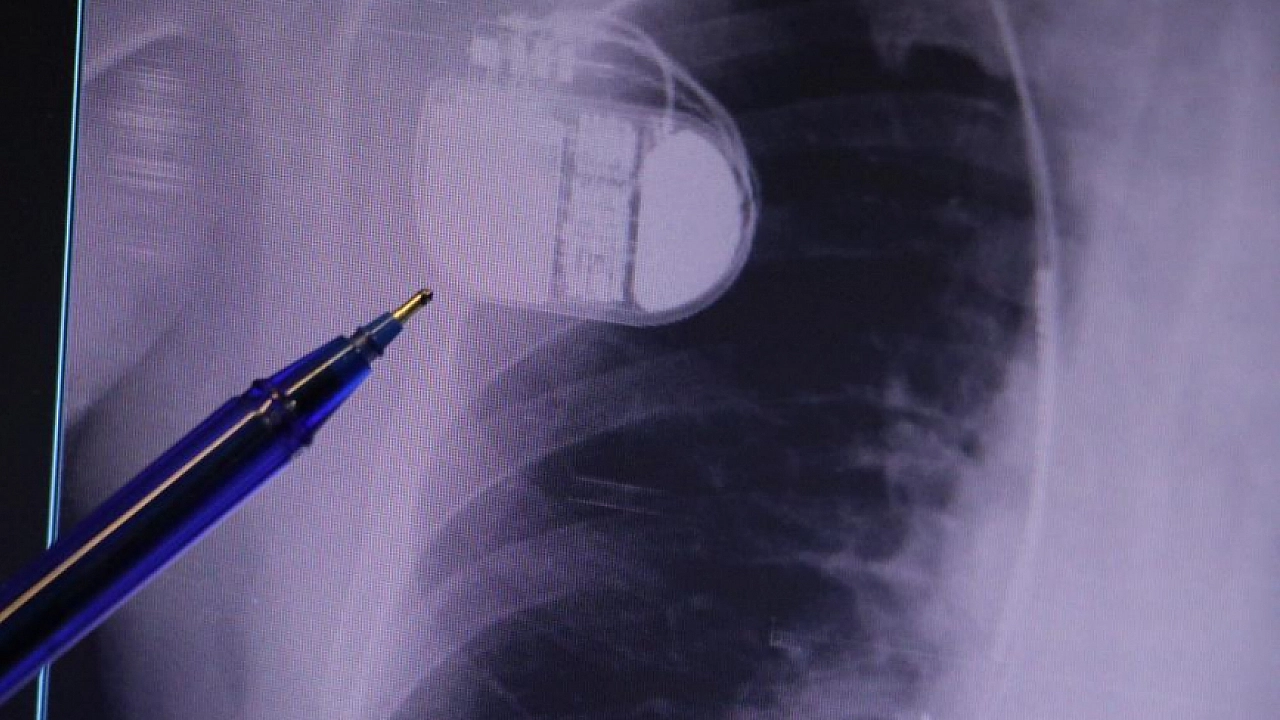

Konuya ilişkin açıklamalarda bulunan Sivas Medicana Hastanesi Kardiyoloji Bölümü Uzmanı Dr. İsmail Erdoğu, kalp pilinin önemine vurgu yaptı. Erdoğu, Yeni nesil kalp pillerinin MR cihazlarına girmeye imkan sağladığı, ancak tarama cihazlarından geçmenin önerilmediğini ifade ederek, "Soğuk hava nedeniyle oluşan titremeler, kalp pilinin kalbin durduğunu sanmasına ve yanlış şoklamaya yol açabilir. Bu nedenle hastalarımızın bu dönemlerde daha dikkatli olmalarını öneriyoruz" dedi.

Kalp pilleri ile MR cihazına girilebileceğini belirten Erdoğu, "Çok büyük bir ameliyat değil ama yine de ciddi bir cerrahi işlem. Kalp pili, tıpta son 30 yılda yaşanan gelişmelerden en büyüğü. Bir bilgisayarın küçültülüp insan vücuduna konulmuş hali aslında. İnsan ömrünü ciddi oranda uzatan bir tedavi. İnsanlar bir şokla hayata tutunurken, pil olmasaydı öleceğini düşündüğümüz birçok hastamız var. Kalp pilinin bu özelliği, uygun hastalarda ciddi oranda ani ölümü engelliyor. Hastanın başına gelecek bir kalp durması durumunda yanında bir sağlıkçı yoksa, onun ritmini düzeltecek defibrilatör cihazı yoksa hastayı hayatta tutmak mümkün değil. Uygun endikasyonlarda kalp pili olduğu zaman, pil hastaların ritmini algılıyor ve acilde yapılan şoklamayı yaparak hastayı hayata döndürüyor. Kalp pillerinde yeni teknolojilerle MR'a girmek mümkün, tomografiye zaten girebiliyorlar. Tarama cihazlarından geçmelerini uygun görmüyoruz. Bu tarz durumlarda hastalarımız 'kalp pilim var' dediğinde muaf tutuluyorlar. Kalp pilleri ciddi teknolojik cihazlardır. Vücudun içindeki titreşimi, örneğin mikser kullanmak, kolunu sallayacak herhangi bir eylem kalp pilinde olumsuz etki oluşturabilir. Soğuk havalarda vücutta oluşan ciddi titremeler kalp pilinin hafızasını karıştırıp kalbin durduğunu düşündürebilir ve gereksiz şoklama yapabilir. Bu tarz kişilerin soğuk havalarda daha temkinli olması gerekir" diye konuştu.